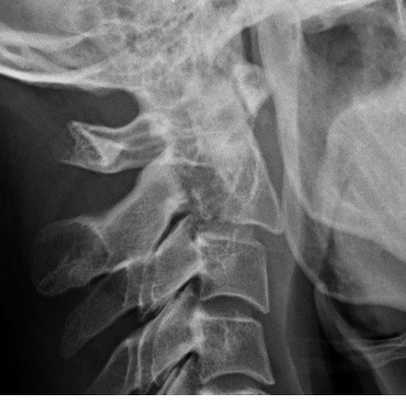

Рентгенограмма. Подвывих в шейном отделе позвоночника. Цветовая обработка изображения.

Половина всех случаев переломов позвоночника приходится на шейный отдел. Многие травмы шейного отдела позвоночника угрожают жизни пациента для жизни пациента. Поэтому они требуют неотложных мероприятий.

Обследование начинается со стандартной рентгенографии в 3 проекциях – боковой, передне-задней (прямой) и через рот.